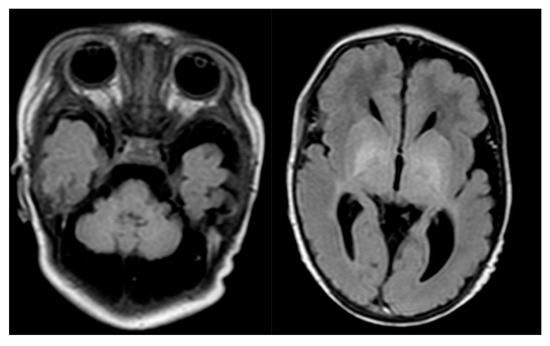

Figure 1. Proband’s brain MR. Cerebellar hypoplasia and dilated cerebellar fluid spaces.

brain MR

(5th day after birth, Figure 1)

cerebellar hypoplasia and dilated cerebellar fluid spaces

slightly enlarged cerebral fluid spaces in the left temporal region

a discrete band of enhanced signal in T1-dependent images and FLAIR within one of the grooves of the left frontal lobe (after the bleeding?)

the supratentorial ventricular system symmetrically widened within the lateral ventricle (Evans index - 0.36)